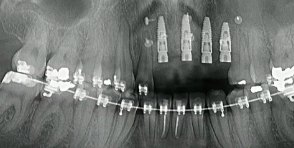

CLINICAL VIDEO All-on-4 Upper Jaw Implant Surgery - Surgical steps, Implant Plac

CAT# CV-052

All-on-4 Upper Jaw Implant Surgery - Surgical steps, Implant Placement, 3D treatment planning and immediate fixed hybrid prostheses delivery (Part 2)

Dr. Sascha Jovanovic